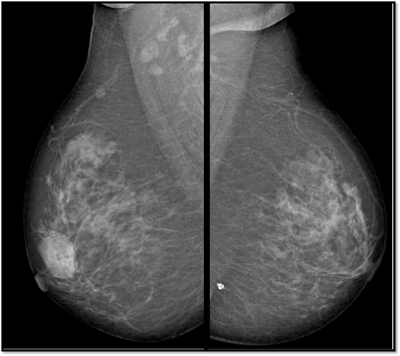

38 year old lady with right breast lump of one year duration.

What is the diagnosis based on mammography and tomosynthesis?